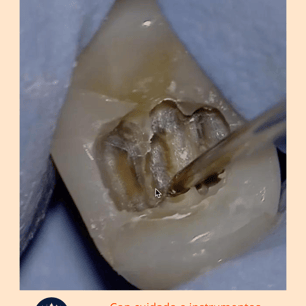

Localización y Remoción de

Calcificaciones: Se utilizan instrumentos especiales, como limas ultrasonicas, para localizar y remover las calcificaciones.

Limpieza y Desinfección: El conducto radicular se limpia y desinfecta una vez que las calcificaciones se han eliminado.